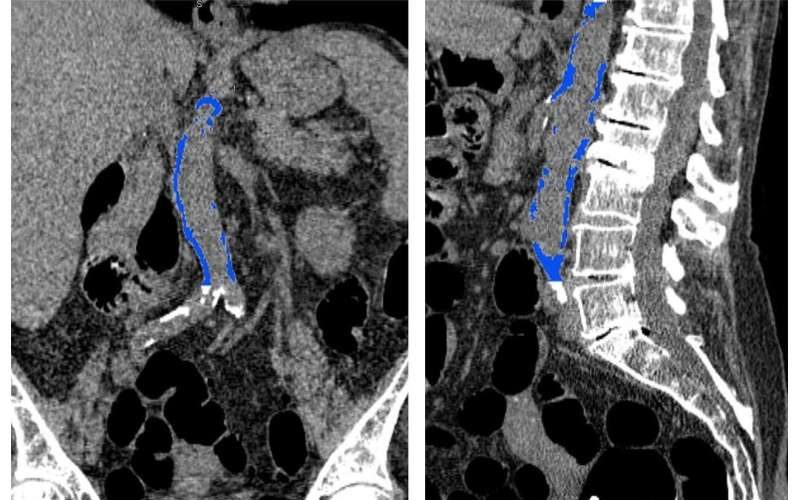

AAC can be detected easily using lateral spine scans from bone density machines – routinely used to screen for osteoporosis. But finding AAC in these scans can require specialist readers and equipment.

As Associate Professor Lewis told TND: “Very extensive AAC is generally quite quick and easy to identify,” he said.

“However smaller areas of AAC can be challenging to identify and differentiate from imaging artefacts, such as overlying structures and bowel gas. You also need to assess these on specialised monitors in dark rooms.”

This can take between five and 15 minutes for each image.

To solve this issue, Dr Lewis and company turned to AI machine learning. More than 5000 images were used to train and test what’s known as a convolutional neural network algorithm.

A new ECU study developed software that is able to analyse about 60,000 images in a single day. The misdiagnosis rate was a mere 3 per cent – and the algorithms are a work in progress.